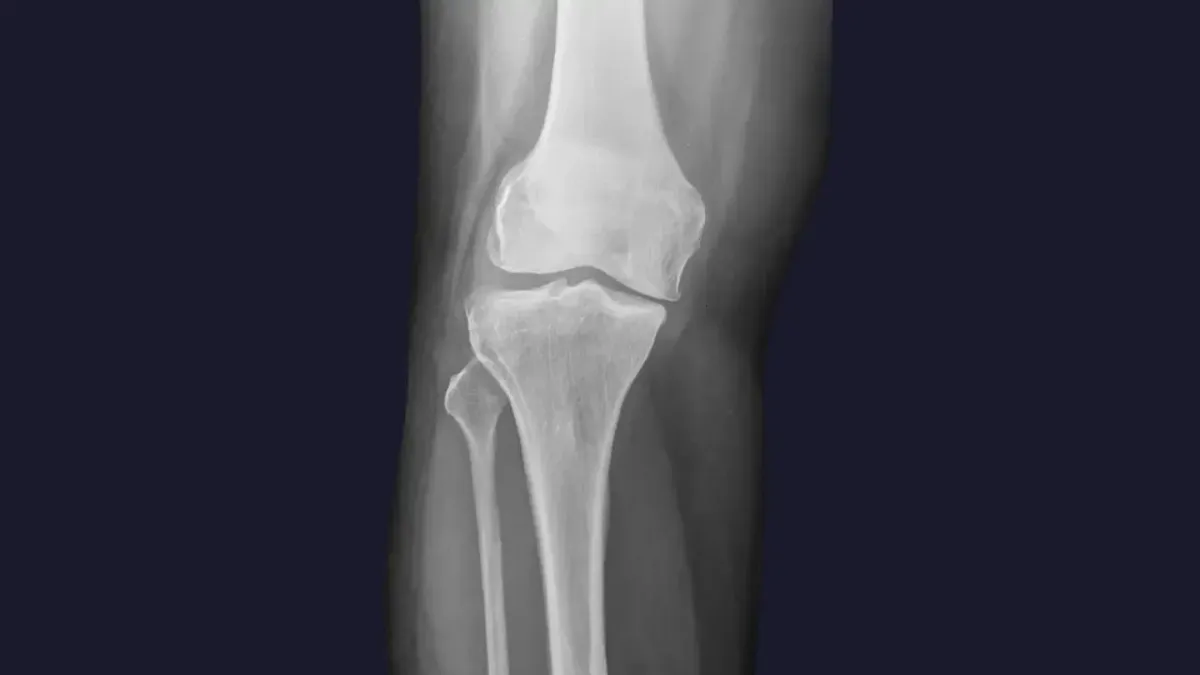

Knee pain is a widespread complaint, often stemming from a variety of sources. Here are some of the common culprits we see in Tupelo, MS. :

Misalignment: Even subtle misalignments in the knee joint itself, or in the hips and pelvis, can lead to improper tracking of the kneecap, increased wear and tear, and pain.

Arthritis: Degenerative changes in the knee joint can cause stiffness, swelling, and chronic pain.

Ligament or Meniscus Issues: While severe tears may require surgical intervention, chiropractic care can help manage pain and improve function for less severe injuries by optimizing joint mechanics and supporting the healing process.

Poor Biomechanics: Imbalances in the muscles surrounding the knee, or issues with foot mechanics, can place excessive stress on the joint.